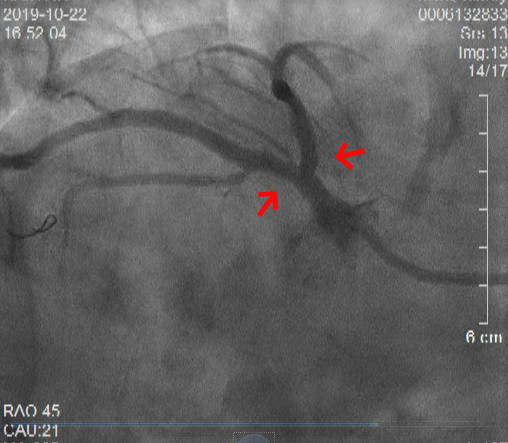

术后冠状动脉造影显示:前降支和回旋支开口处病变解除